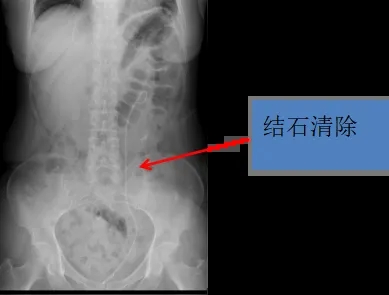

“双镜”即经皮肾镜+经尿道输尿管镜,一期手术解决患者的复杂、多发泌尿系结石,手术成功去除了多发输尿管结石以及肾下盏结石,解除了输尿管梗阻,挽救了患侧肾功能,治疗效果满意,已经顺利出院。

经过充分的术前准备,患者取截石位,经尿道输尿管镜下逆行上行利用钬激光将输尿管结石粉末化,查无结石残留;调整体位为俯卧位,经肾造瘘口置入肾镜鞘,寻找肾结石,钬激光将结石击碎取出,手术历经1个小时顺利完成,术后复查输尿管梗阻已解除,无结石残留,肾积水消失、左肾功能恢复。患者及家属对手术效果非常满意。